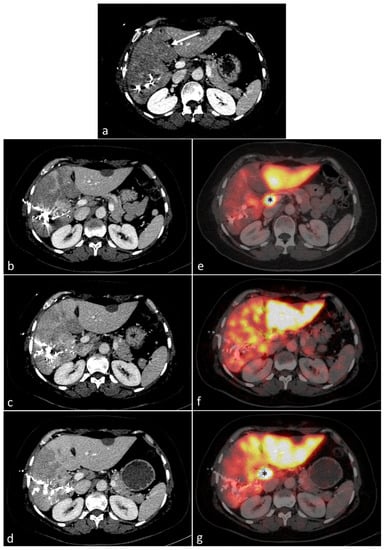

3.2. Deportalized Liver (S5-8 after PVE)

3.3. Venous-Deprived Liver (S5-8 after eLVD)

3.4. Congestive Liver (S4 after eLVD)